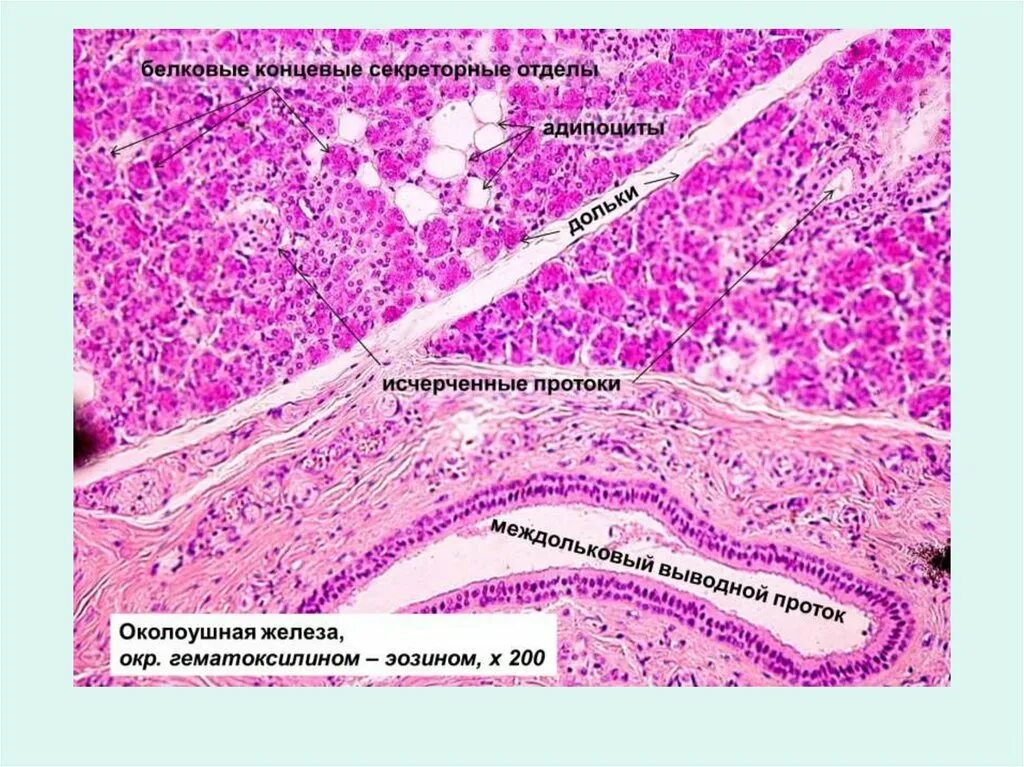

Околоушная гистология